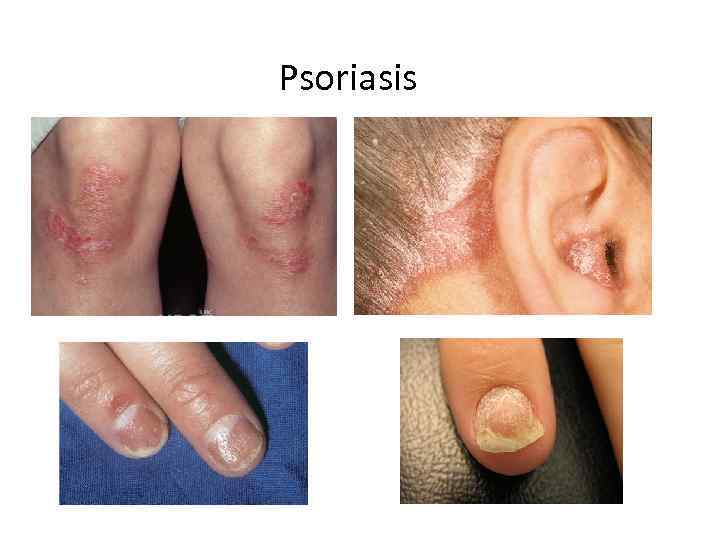

Psoriasis